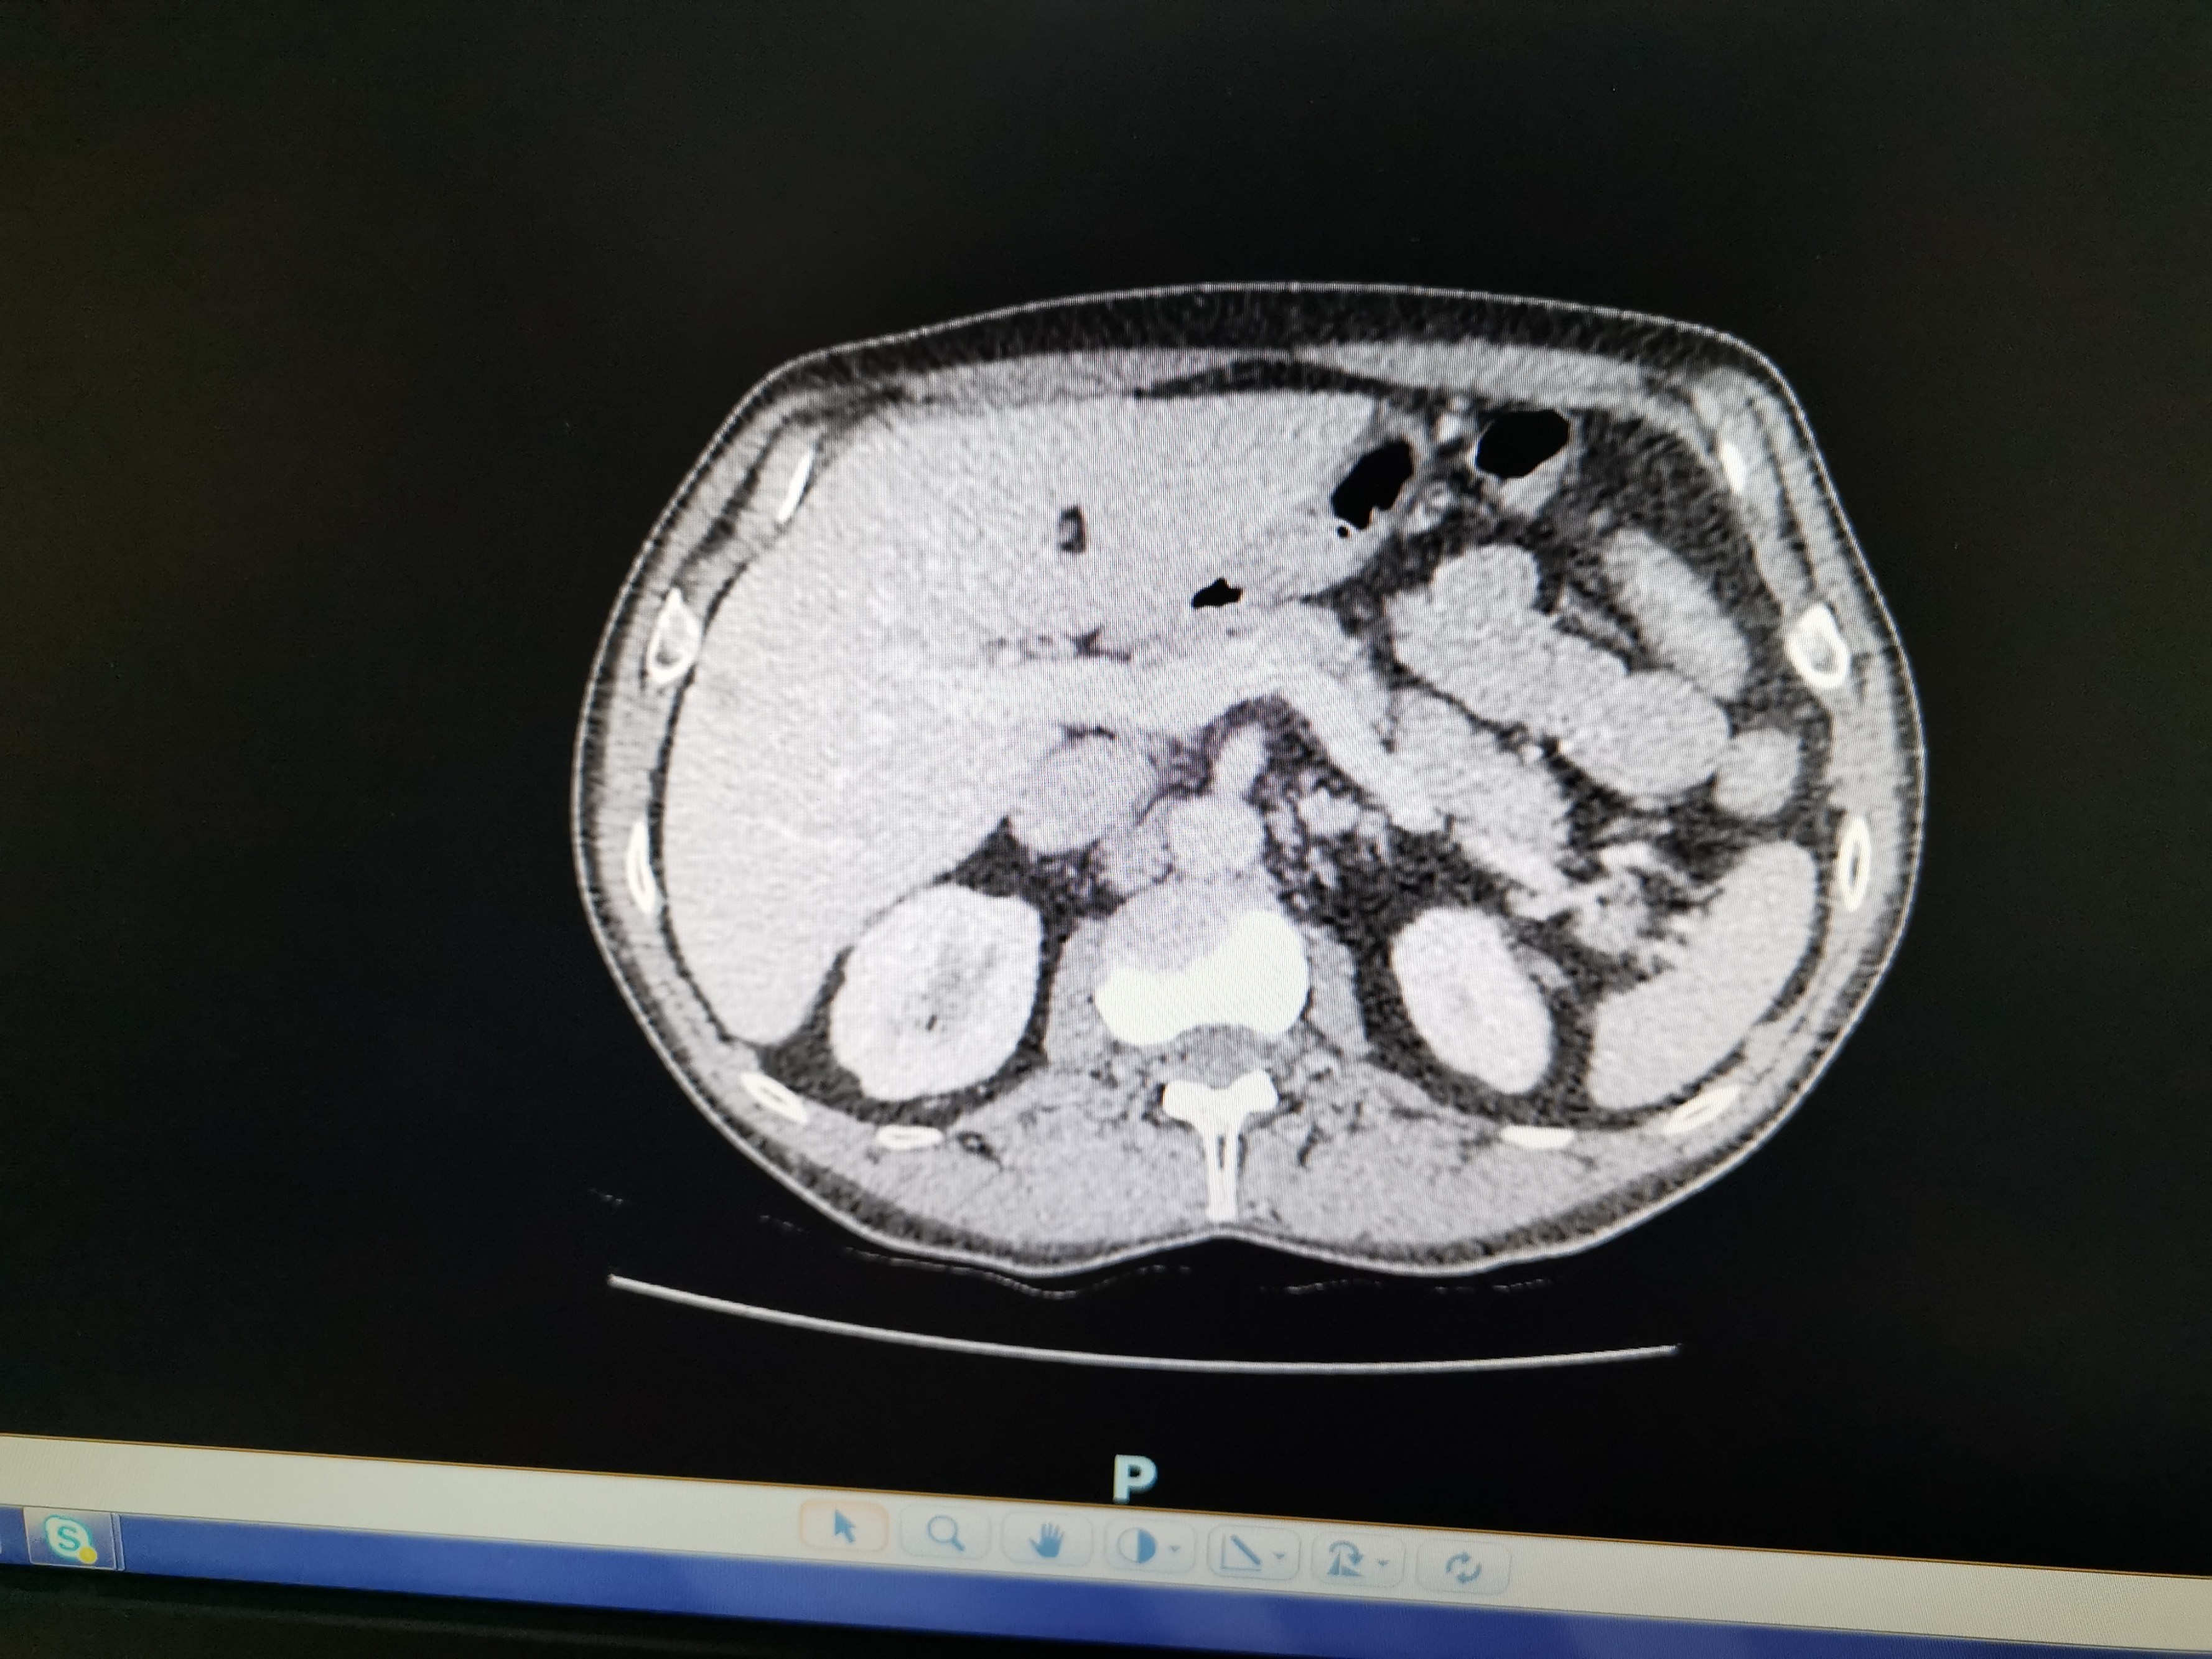

So for now, here’s a photo I took of the consultant’s screen the other week. The spot in question is the small, very slightly darker grey bit in the middle on the right. See, tiny. Hardly worth bothering with really. Except of course they are, thankfully.

Seems they have decided the spot on the liver has metastasised, ie it is cancerous, which means an operation in Bristol at some point in the next few weeks. It is a very small spot, and it is on the surface, so it’s an ‘easy’ operation he said, and may not need chemo beforehand, but we won’t know this or the many other new variables for another week or two, while YDH and Bristol work out a plan between them. The variables are these –

So, the only new thing we know for sure is that the spot on the liver is cancerous. Of course, this all makes things rather more complicated logistically, but at least there will be a few weeks before anything happens, hopefully giving Julie time to recover a little from her own cancer treatment, which ended today (hurrah!). So not ideal news, but at least it’s got rid of one unknown.

All of which means Bernard is now T3N0M1, or Stage 4, but I have absolutely no doubt that he can be beaten, it’ll just take a little longer is all.